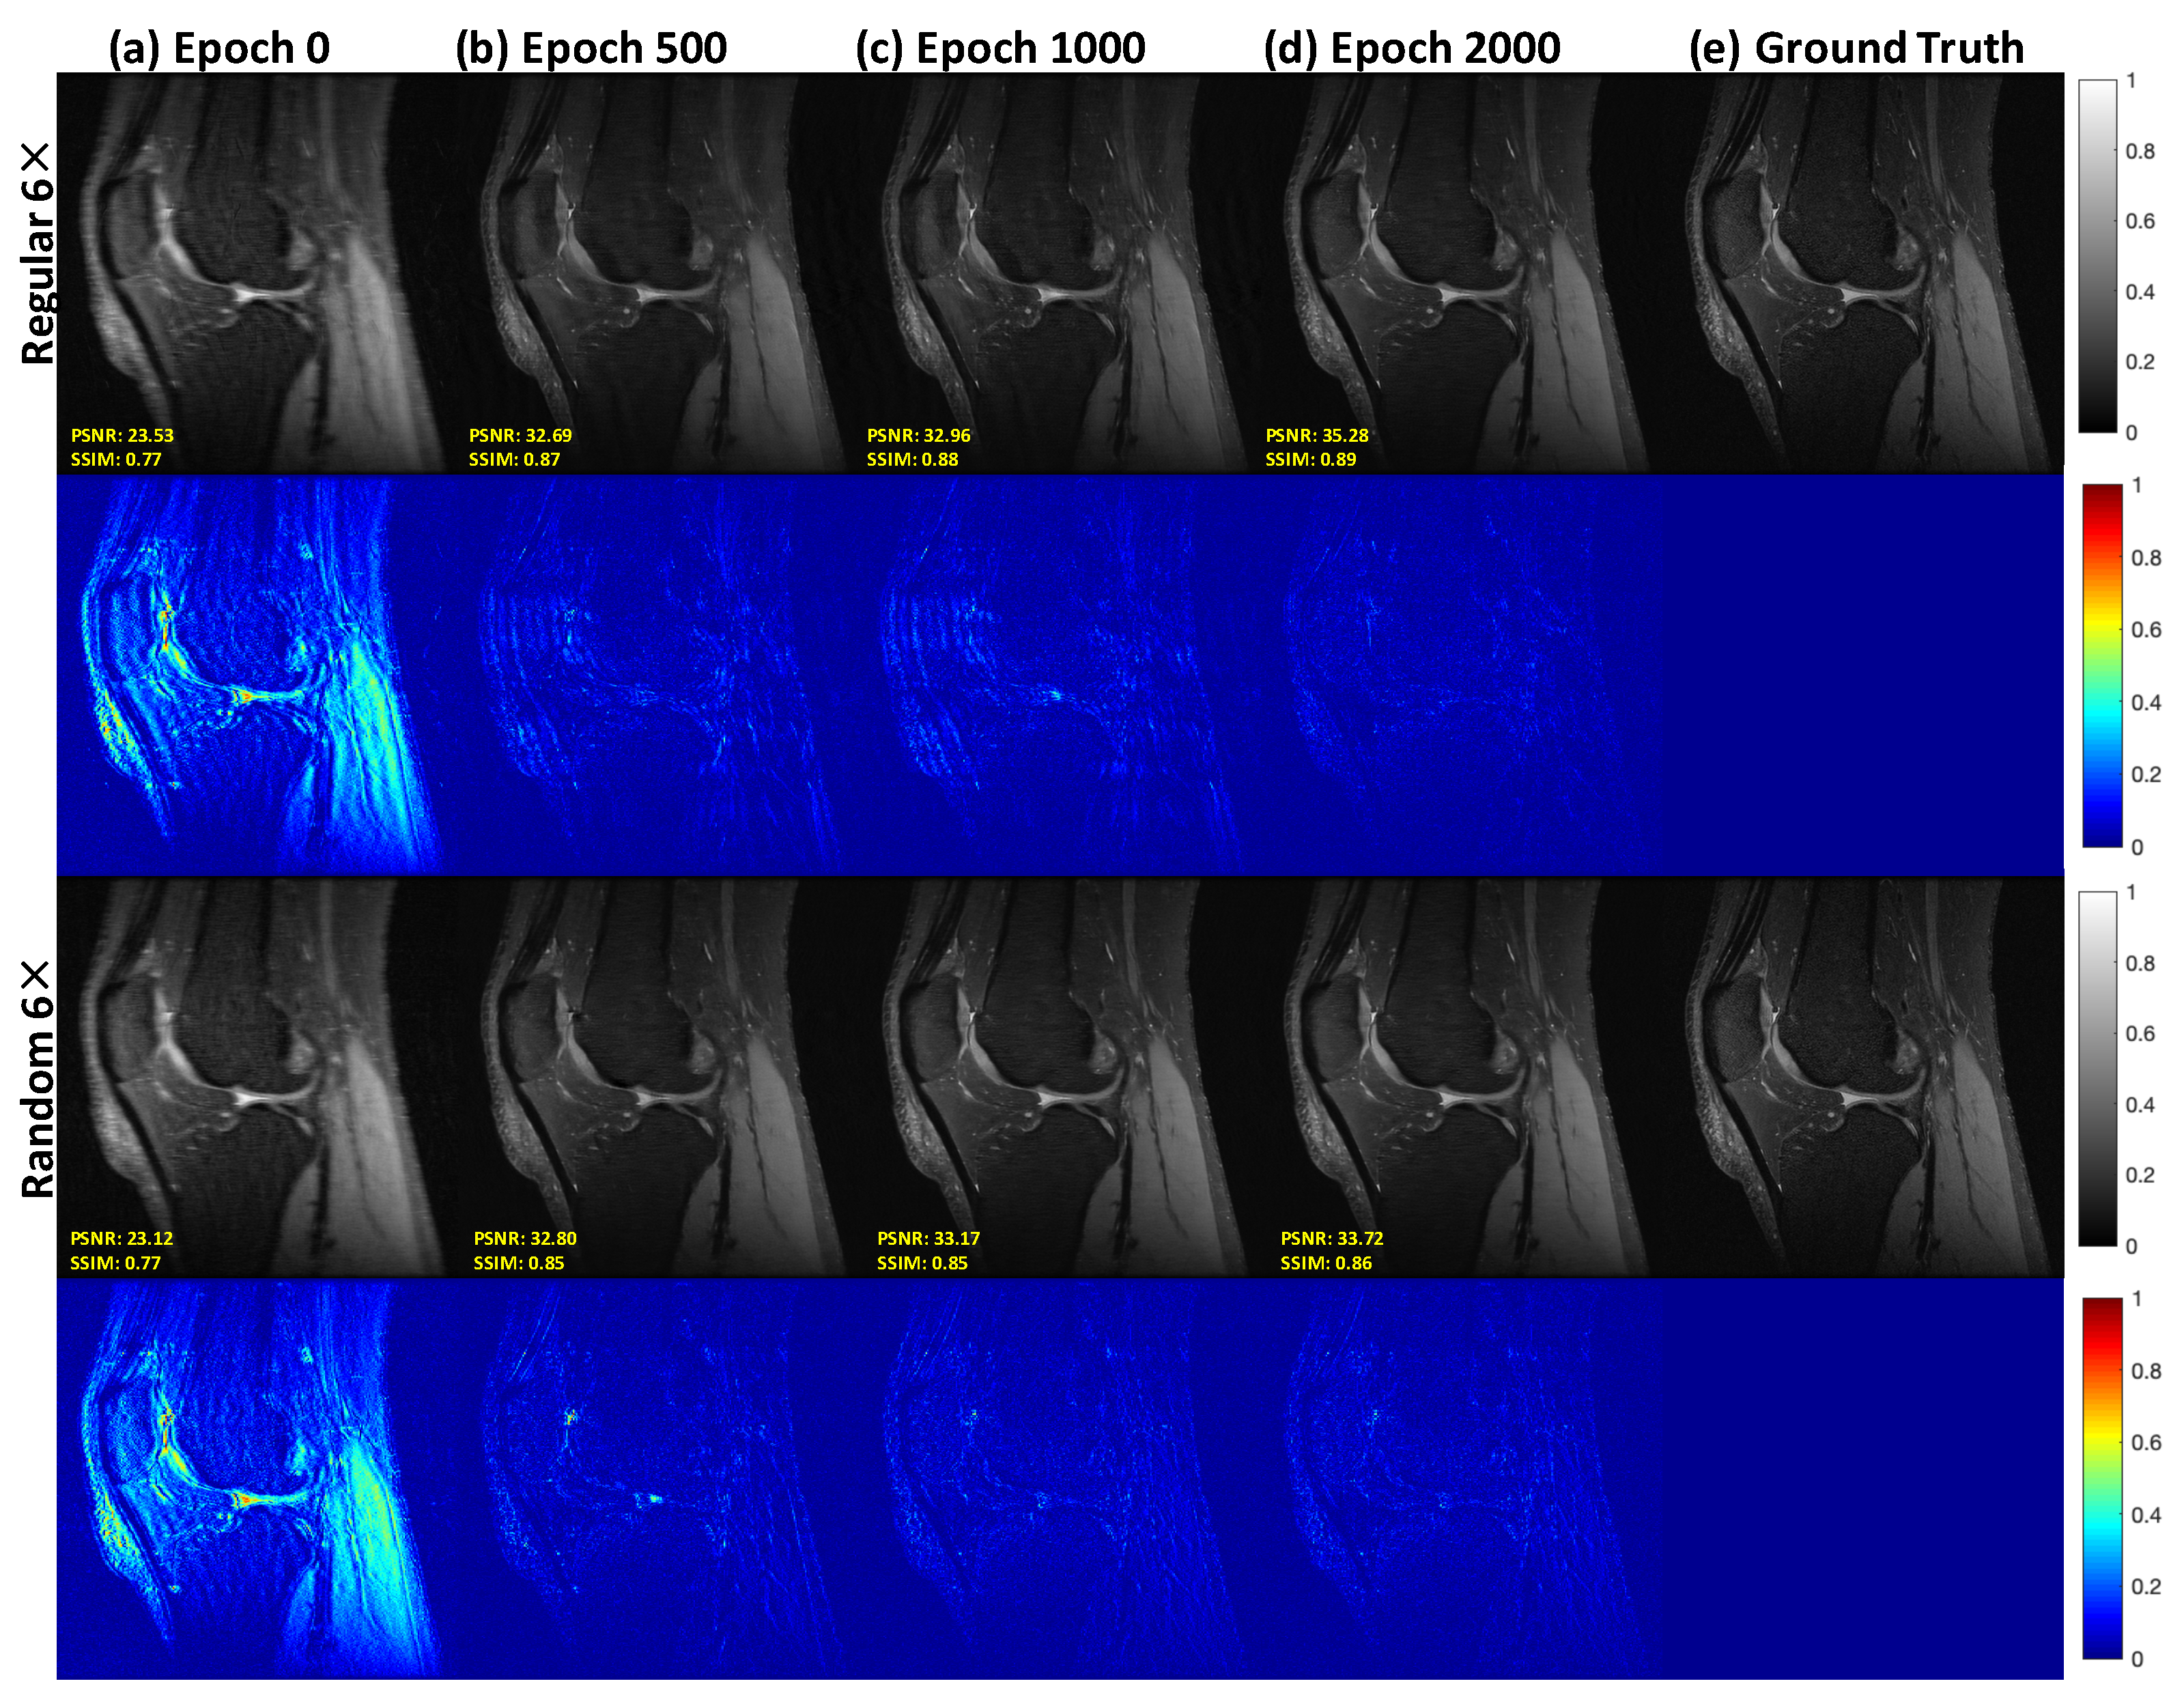

3.2. Reconstruction Results: Knee MRI Data